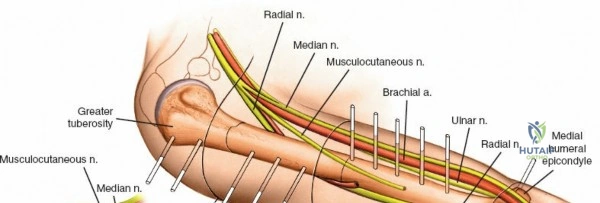

The humerus presents significant challenges due to the course of the radial nerve, axillary nerve, and brachial artery.

* Proximal Third: The safe zone is located laterally. Pins can be placed from lateral to medial, avoiding the axillary nerve, which runs transversely approximately 5 to 7 cm distal to the lateral acromion.

* Middle Third: This is the most hazardous region. The radial nerve spirals from posterior to anterior along the spiral groove. Anterolateral pin placement is generally safe if placed distal to the deltoid insertion, but open dissection to the periosteum is mandatory.

* Distal Third: The radial nerve pierces the lateral intermuscular septum to enter the anterior compartment. Pins are typically placed posteriorly or posterolaterally, directly through the triceps tendon or muscle belly, ensuring the radial nerve is protected anteriorly.

Humeral external fixation is most frequently utilized for damage control in polytrauma or for severe open fractures.

Proximal Humerus Pin Placement

1. Identify the safe zone on the lateral aspect of the proximal humerus, distal to the axillary nerve.

2. Make a longitudinal incision over the lateral aspect of the greater tuberosity or proximal diaphysis.

3. Bluntly dissect through the deltoid muscle fibers down to the bone.

4. Insert the drill sleeve, pre-drill with a 3.5 mm or 4.0 mm bit, and insert a 5.0 mm half pin.

5. Confirm bicortical purchase with fluoroscopy.

Distal Humerus Pin Placement

1. The distal pins are typically placed posteriorly to avoid the radial nerve.

2. Make a longitudinal incision over the posterior aspect of the distal humerus, proximal to the olecranon fossa.

3. Split the triceps bluntly down to the periosteum.

4. Insert the tissue protector, pre-drill, and place the 5.0 mm pins from posterior to anterior.

5. Ensure the pins do not penetrate the anterior cortex excessively to avoid injury to the brachial artery or median nerve.